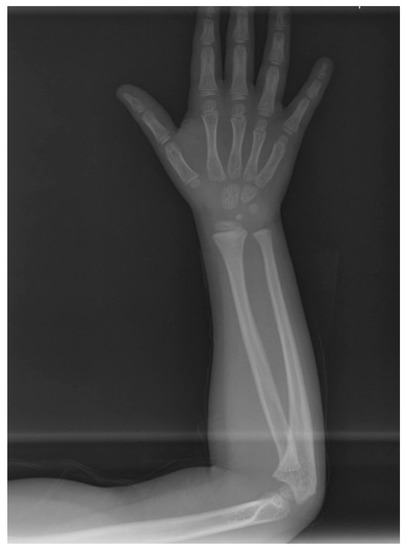

The orthodontic treatment was initiated with the canine exposure (Figure 5) and traction with light forces using a custom-made trans-palatal arch for anchorage purposes (Figure 6 and Figure 7). An open surgical technique (apically positioned flap) was used to expose the labially positioned right canine and a closed technique for the left, which was positioned palatally. Sectional mechanics were applied during treatment until the eruption of all permanent teeth (Figure 8). The upper lateral incisors were extracted after the successful eruption of the impacted canines and for aesthetic reasons. Subsequently, comprehensive orthodontic treatment was performed using fixed 0.018-inch-slot edgewise appliances. A lower lingual arch was placed to preserve the leeway space thus helping with the lower crowing. The progression of the archwire sequence was from 0.014-inch nickel-titanium to 0.016-inch Australian archwires. Class III light elastic forces were used bilaterally to help with space closure on the upper arch.

Figure 8. Sectional mechanics used for the traction of the impacted canines.